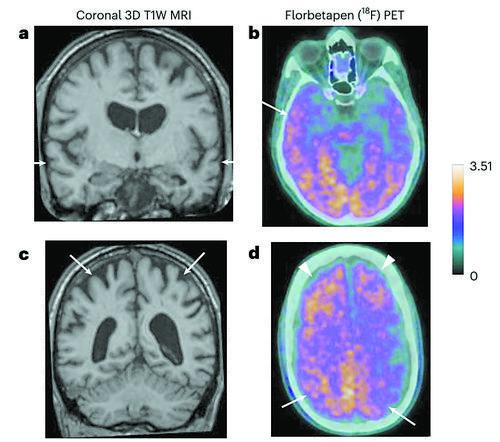

磁共振和淀粉样蛋白PET图像。图片来源:《自然·医学》

其中5人出现了与早发性痴呆(症状出现于38—55岁)一致的症状,符合阿尔茨海默病的诊断标准(在两个或两个以上认知领域出现进展性障碍,严重程度足以影响日常活动)。其余3人中,一人出现了符合中度认知障碍诊断标准的症状(开始于42岁),另一人仅有主观认知症状,第三人无症状。

生物标志物分析在无症状时不能用于诊断阿尔茨海默病,但可以支持两名确诊患者的诊断,并表明另一人已出现阿尔茨海默病的迹象。团队还对两名研究期间去世的人做了尸检,包括大量脑组织取样,其中一名患者也显示出阿尔茨海默病的病理。